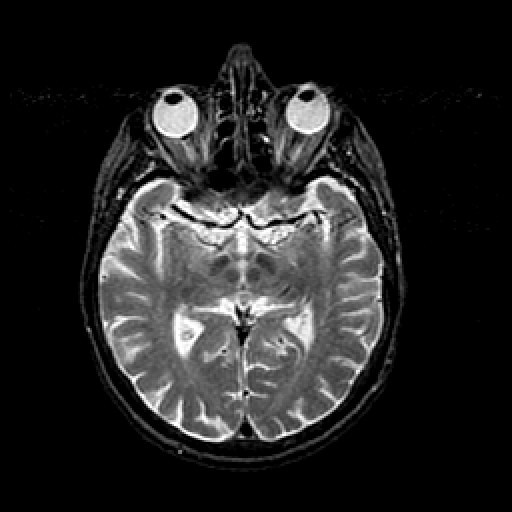

T2-weighted structural MR: Slice 24

Slice 24